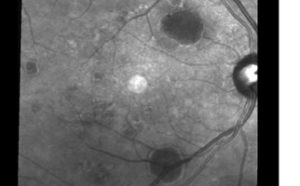

Slit lamp exam revealed a 1+ nuclear sclerotic cataract OD and a 3+ nuclear sclerotic cataract OS, which was the cause of reduced vision OS. All other anterior segment findings were unremarkable. Healthy optic nerves with cup-to-disc ratios of 0.45 OD and 0.50 OS were assessed on fundoscopy. Additionally, several well-delineated, round, orange-reddish posterior pole lesions were observed OU, but were more pronounced OD. These lesions appeared subretinal and extrafoveal and were not associated with other retinal findings.

Optical coherence tomography (OCT) images were acquired OU. While center macular thickness, measuring 248 microns OD and 238 microns OS, and foveal contour were normal OU, multiple extrafoveal PEDs corresponding with the lesions noted on fundoscopy were visualized on the scans. Of note was a large PED with overlying SRF that was approximately 0.75 disc diameters in size and located superonasal to the macula OD (Figures 1 and 2). An additional PED of approximately the same size was present just inferior to the macula, and a third, smaller PED was visualized temporal to the macula OD. OS images revealed a few small PEDs in the superior, inferior and temporal macula, none of which were associated with SRF (Figure 3). All PED findings on OCT were consistent with serous PED, which typically appears dome-shaped and well-delineated with an elevated, hyper-reflective RPE overlying a hyporeflective and optically empty space.2,8,9

![]() Figure 2. Larger gray-scale image of the right posterior pole. The dark, round lesions are the pigment epithelial detachments noted on exam and confirmed with optical coherence tomography. Click to enlarge |